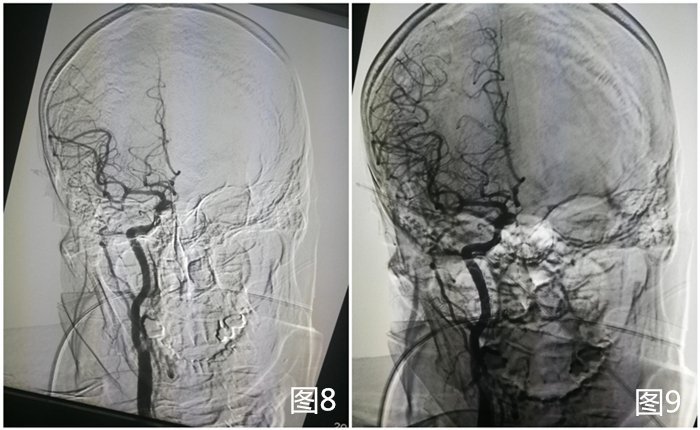

术后再次造影,可见右侧颈总动脉完全通畅(图8、图9)。